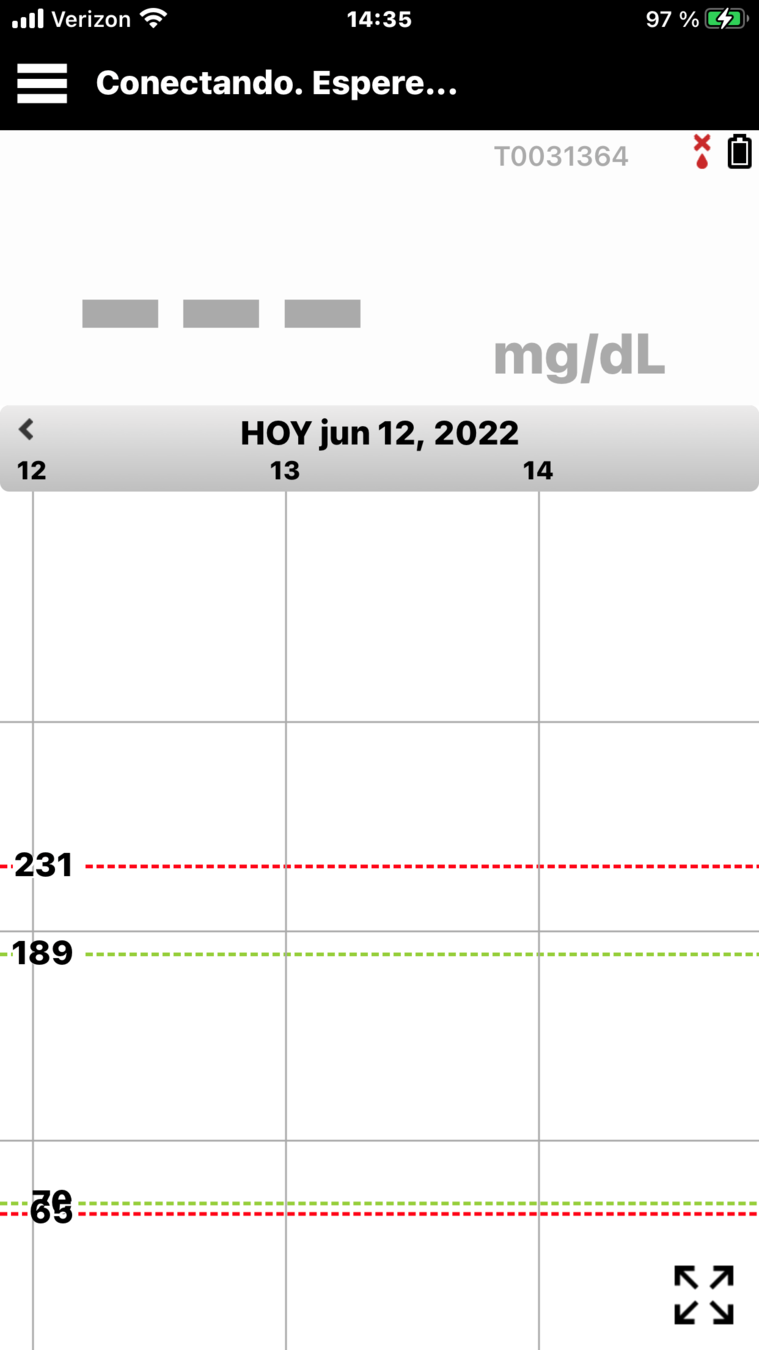

Primero, revisemos la pantalla de inicio

Mi glucosa en la aplicación para móvil Eversense®.

PANTALLA DE INICIO MI GLUCOSA

Cuando abre la aplicación para móvil Eversense®,

se muestran principalmente su nivel

de glucosa actual y una flecha de tendencia.

PANTALLA DE INICIO MI GLUCOSA

Primero, revisemos la pantalla de inicio

Mi glucosa en la aplicación para móvil Eversense®.

En la parte superior derecha, puede ver

la intensidad de la conexión entre el transmisor y el sensor, y la carga de la batería que tiene

el transmisor.

PANTALLA DE INICIO MI GLUCOSA

Primero, revisemos la pantalla de inicio

Mi glucosa en la aplicación para móvil Eversense®.

Cuando abre la aplicación para móvil Eversense®,

se muestran principalmente su nivel

de glucosa actual y una flecha de tendencia.

Si ha activado la función No molestar o Perfil temporal, aparecerán los iconos correspondientes

en la parte superior izquierda.

PANTALLA DE INICIO MI GLUCOSA

Y, en la parte inferior, se encuentra el gráfico de tendencia de la glucosa.

Las líneas discontinuas rojas indican los niveles de alerta de glucosa alta y baja, y las líneas discontinuas verdes indican el intervalo objetivo.

Todos los eventos que introduzca en la aplicación (como una calibración, comida, ejercicio

o insulina) o las alertas que reciba, se mostrarán en el gráfico de tendencia con un icono.

PANTALLA DE INICIO MI GLUCOSA

Si ha activado la función No molestar o Perfil temporal, aparecerán los iconos correspondientes en la parte superior izquierda.

Puede consultar la sección Utilizar la aplicación para móvil en la Guía de consulta rápida del sistema de MCG Eversense® E3 en cualquier momento.